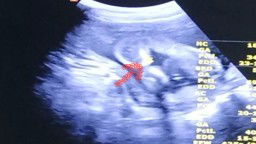

อัลตร้าซาวด์ น้องนอนคว่ำ 20สัปดาห์

ล่าสุดหมอนัด อัลตร้าซาวด์ มาที่ ร.พ.รัฐ อายุครรภ์ 20 W น้องนอนคว้ำแบบนี้ #แต่น้องดิ้นเก่งมากค่ะ ยังไม่รู้เพศ น้องนอนคว่ำแบบนี้ จะเป็นอันตรายไหมค่ะ #ขอคำแนะนำหน่อยค่ะ #ท้องแรกคะ #ขอบคุณสำหรับคำตอบค่ะ